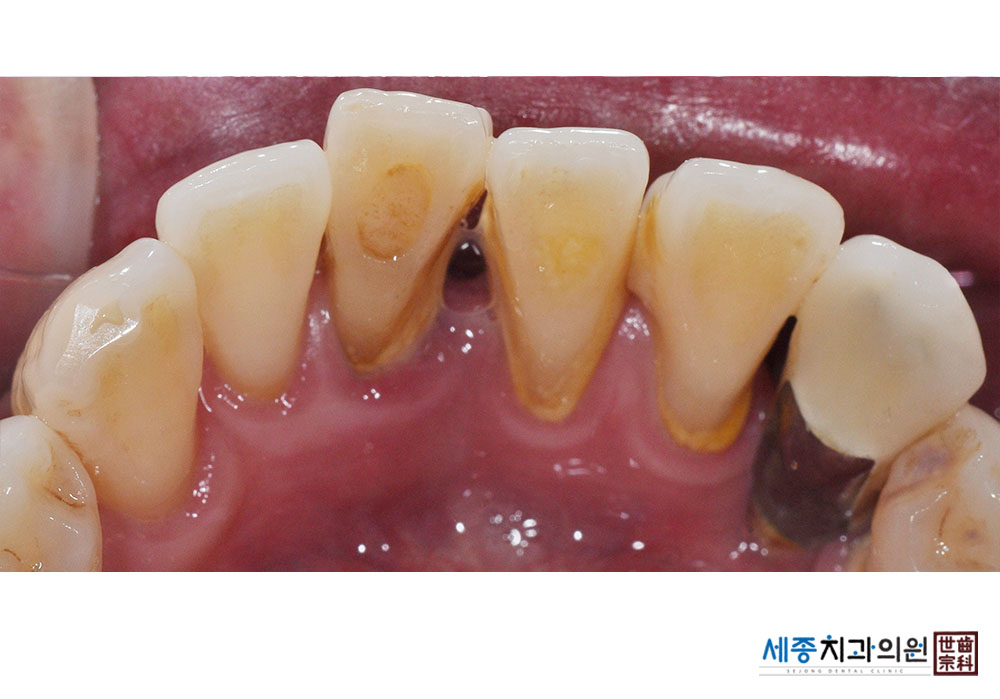

[스케일링] 치주질환 예방 스케일링

치료전 : 2022-12-27

치료후 : 2022-12-27

가글마취&저주파 스켈러를 사용한 스케일링